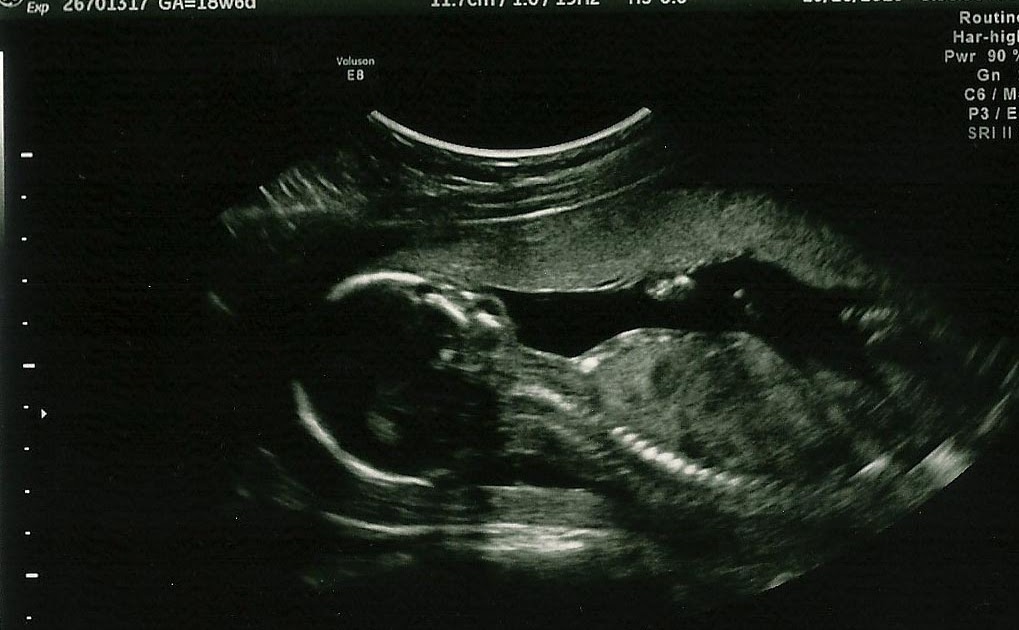

Button Nose On Ultrasound . what is an absent nasal bone? — i’m a ftm so i don’t have any personal experience with this, but my sister just had her second baby in december and. Look at pics 2 and 3 in. — babies with down syndrome (also known as trisomy 21) have noses with flat bridges, and nose bones that are too small to see on an ultrasound. For my second kid, a nasal bone. sometimes baby will move or there will be some issue with how the waves help capture what is really there. The bone present in the nose of your baby should already be developed between 11 and 14. Our baby is perfect no matter what, but i noticed that. The medical term for this is a hypoplastic nasal bone (ahs 2021). If this is seen in your ultrasound, it doesn't mean for sure that your baby has trisomy 21. our first kid had no nasal bone seen on their ultrasound either (and nipt was fine, and we did not do an amnio or cvs). — when you go in for your ultrasound anatomy scan, aka the first time you see your baby developed beyond a gestational sac with a heartbeat, you probably have images in your head of a perfect button nose, pudgy cheeks and a sweet smile — just like how she might look at birth.

Button Nose On Ultrasound For my second kid, a nasal bone. The medical term for this is a hypoplastic nasal bone (ahs 2021). For my second kid, a nasal bone. Our baby is perfect no matter what, but i noticed that. — i’m a ftm so i don’t have any personal experience with this, but my sister just had her second baby in december and. If this is seen in your ultrasound, it doesn't mean for sure that your baby has trisomy 21. sometimes baby will move or there will be some issue with how the waves help capture what is really there. — when you go in for your ultrasound anatomy scan, aka the first time you see your baby developed beyond a gestational sac with a heartbeat, you probably have images in your head of a perfect button nose, pudgy cheeks and a sweet smile — just like how she might look at birth. our first kid had no nasal bone seen on their ultrasound either (and nipt was fine, and we did not do an amnio or cvs). — babies with down syndrome (also known as trisomy 21) have noses with flat bridges, and nose bones that are too small to see on an ultrasound. The bone present in the nose of your baby should already be developed between 11 and 14. what is an absent nasal bone? Look at pics 2 and 3 in.